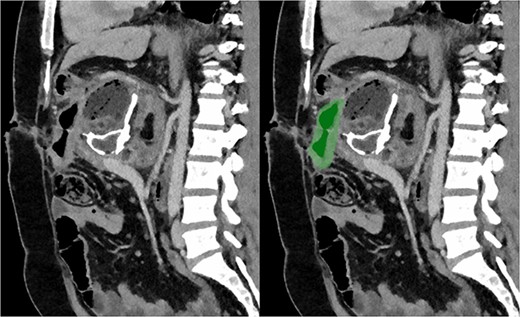

Due to the debilitating nature of the patient’s condition and his wishes for an attempt at treatment, he was brought forward for a further exploratory laparotomy. The patient’s rooftop incision was reopened and the wound and sinus tract were excised en bloc. The stomach and transverse colon were found to be densely adherent to the teratoma. These were carefully mobilized and dissected free from the teratoma. Again, resectability of the teratoma was assessed and deemed to be impossible due to the hepatic artery being inseparable from the lesion (Fig. 2). Instead, internal drainage with diversion of the sinus discharge via a jejunostomy with a Roux en Y reconstruction of the alimentary tract was performed. The jejunum was divided at 50 cm from the duodenojejunal (DJ) flexure and the Roux limb was brought up to the origin of the sinus through a window made in the mesentery of the transverse colon. The lumen was opened and sutured over the origin of the sinus with 4/0 PDS sutures (Fig. 3). Finally, a jejunojejunostomy was formed to return continuity to the jejunum.

Axial section of CT with arterial contrast showing the hepatic artery (red) traversing within the superior aspect of the lesion (green).